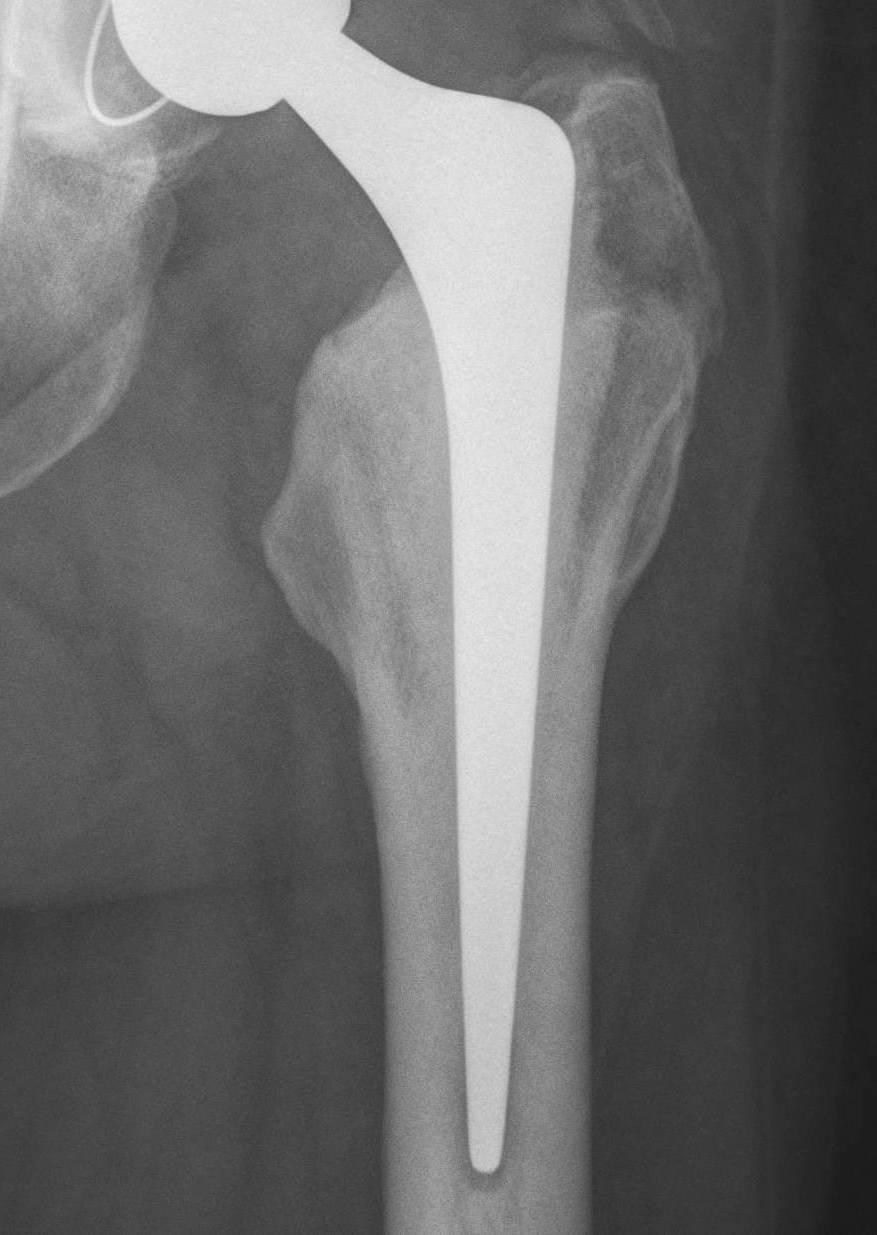

Barrack's femoral component cementation quality grading system

| Grade | Definition |

|---|---|

| A | Complete filling of the medullary canal, without radiolucent lines between the cement and the bone (white-out) |

| B | Radiolucent line covering up to 50% of the cement-bone interface |

| C | Radiolucent line covering between 50% and 99% of the cement-bone interface or incomplete cement mantle |

| D | Complete radiolucent line (100%) at the cement-bone interface and/or absence of cement distally to the end of the stem |

Grade A Grade B Grade C Grade D